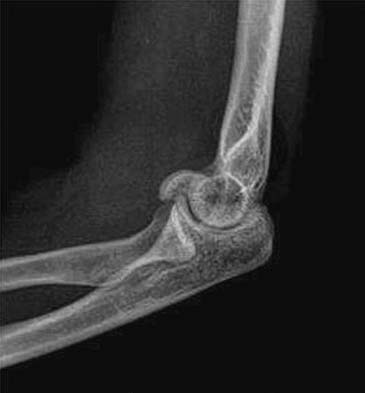

Elbow Dislocation